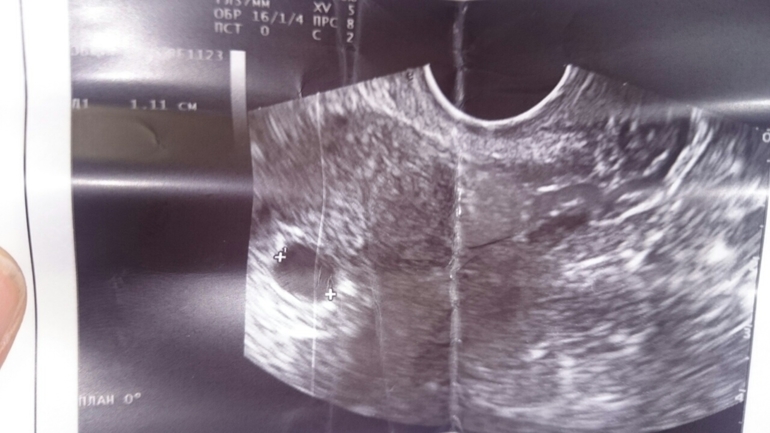

УЗИ она решила делать сама.. и по видимому не имея опыта решила поучиться на мне. В течении УЗИ я услышала вот такие комментарии:

1) ТАААк это внематочная, будем класть…

2) Тааак, вообще ничего нет…

3) Таааак, а что нажать, что бы картинку сделать маленькой..

4) Таак.. ужас какой, что это..

5) Тааак… плодное яйцо!!! Пустое.. А как его развернуть.. хм… А какого размера должно быть яйцо в 5 недель?..А почему пустое то..Да и маленькое какое…

Я не расстроилась. Я была одновременно и разочарована, и расстроена.. Разочарована, от того, что мои надежды таки не оправдались, и с доктором мне не повезло.. опять.. Ну, и как тут не расстроиться, когда твой предположительный гинеколог на ближайшие 9 месяцев не помнит размер плодного яйца в пять недель..

Размер плодного яйца соответствует норме и сроку. То что не видно эмбриона - такое бывает, к тому же аппарат мог быть старый.